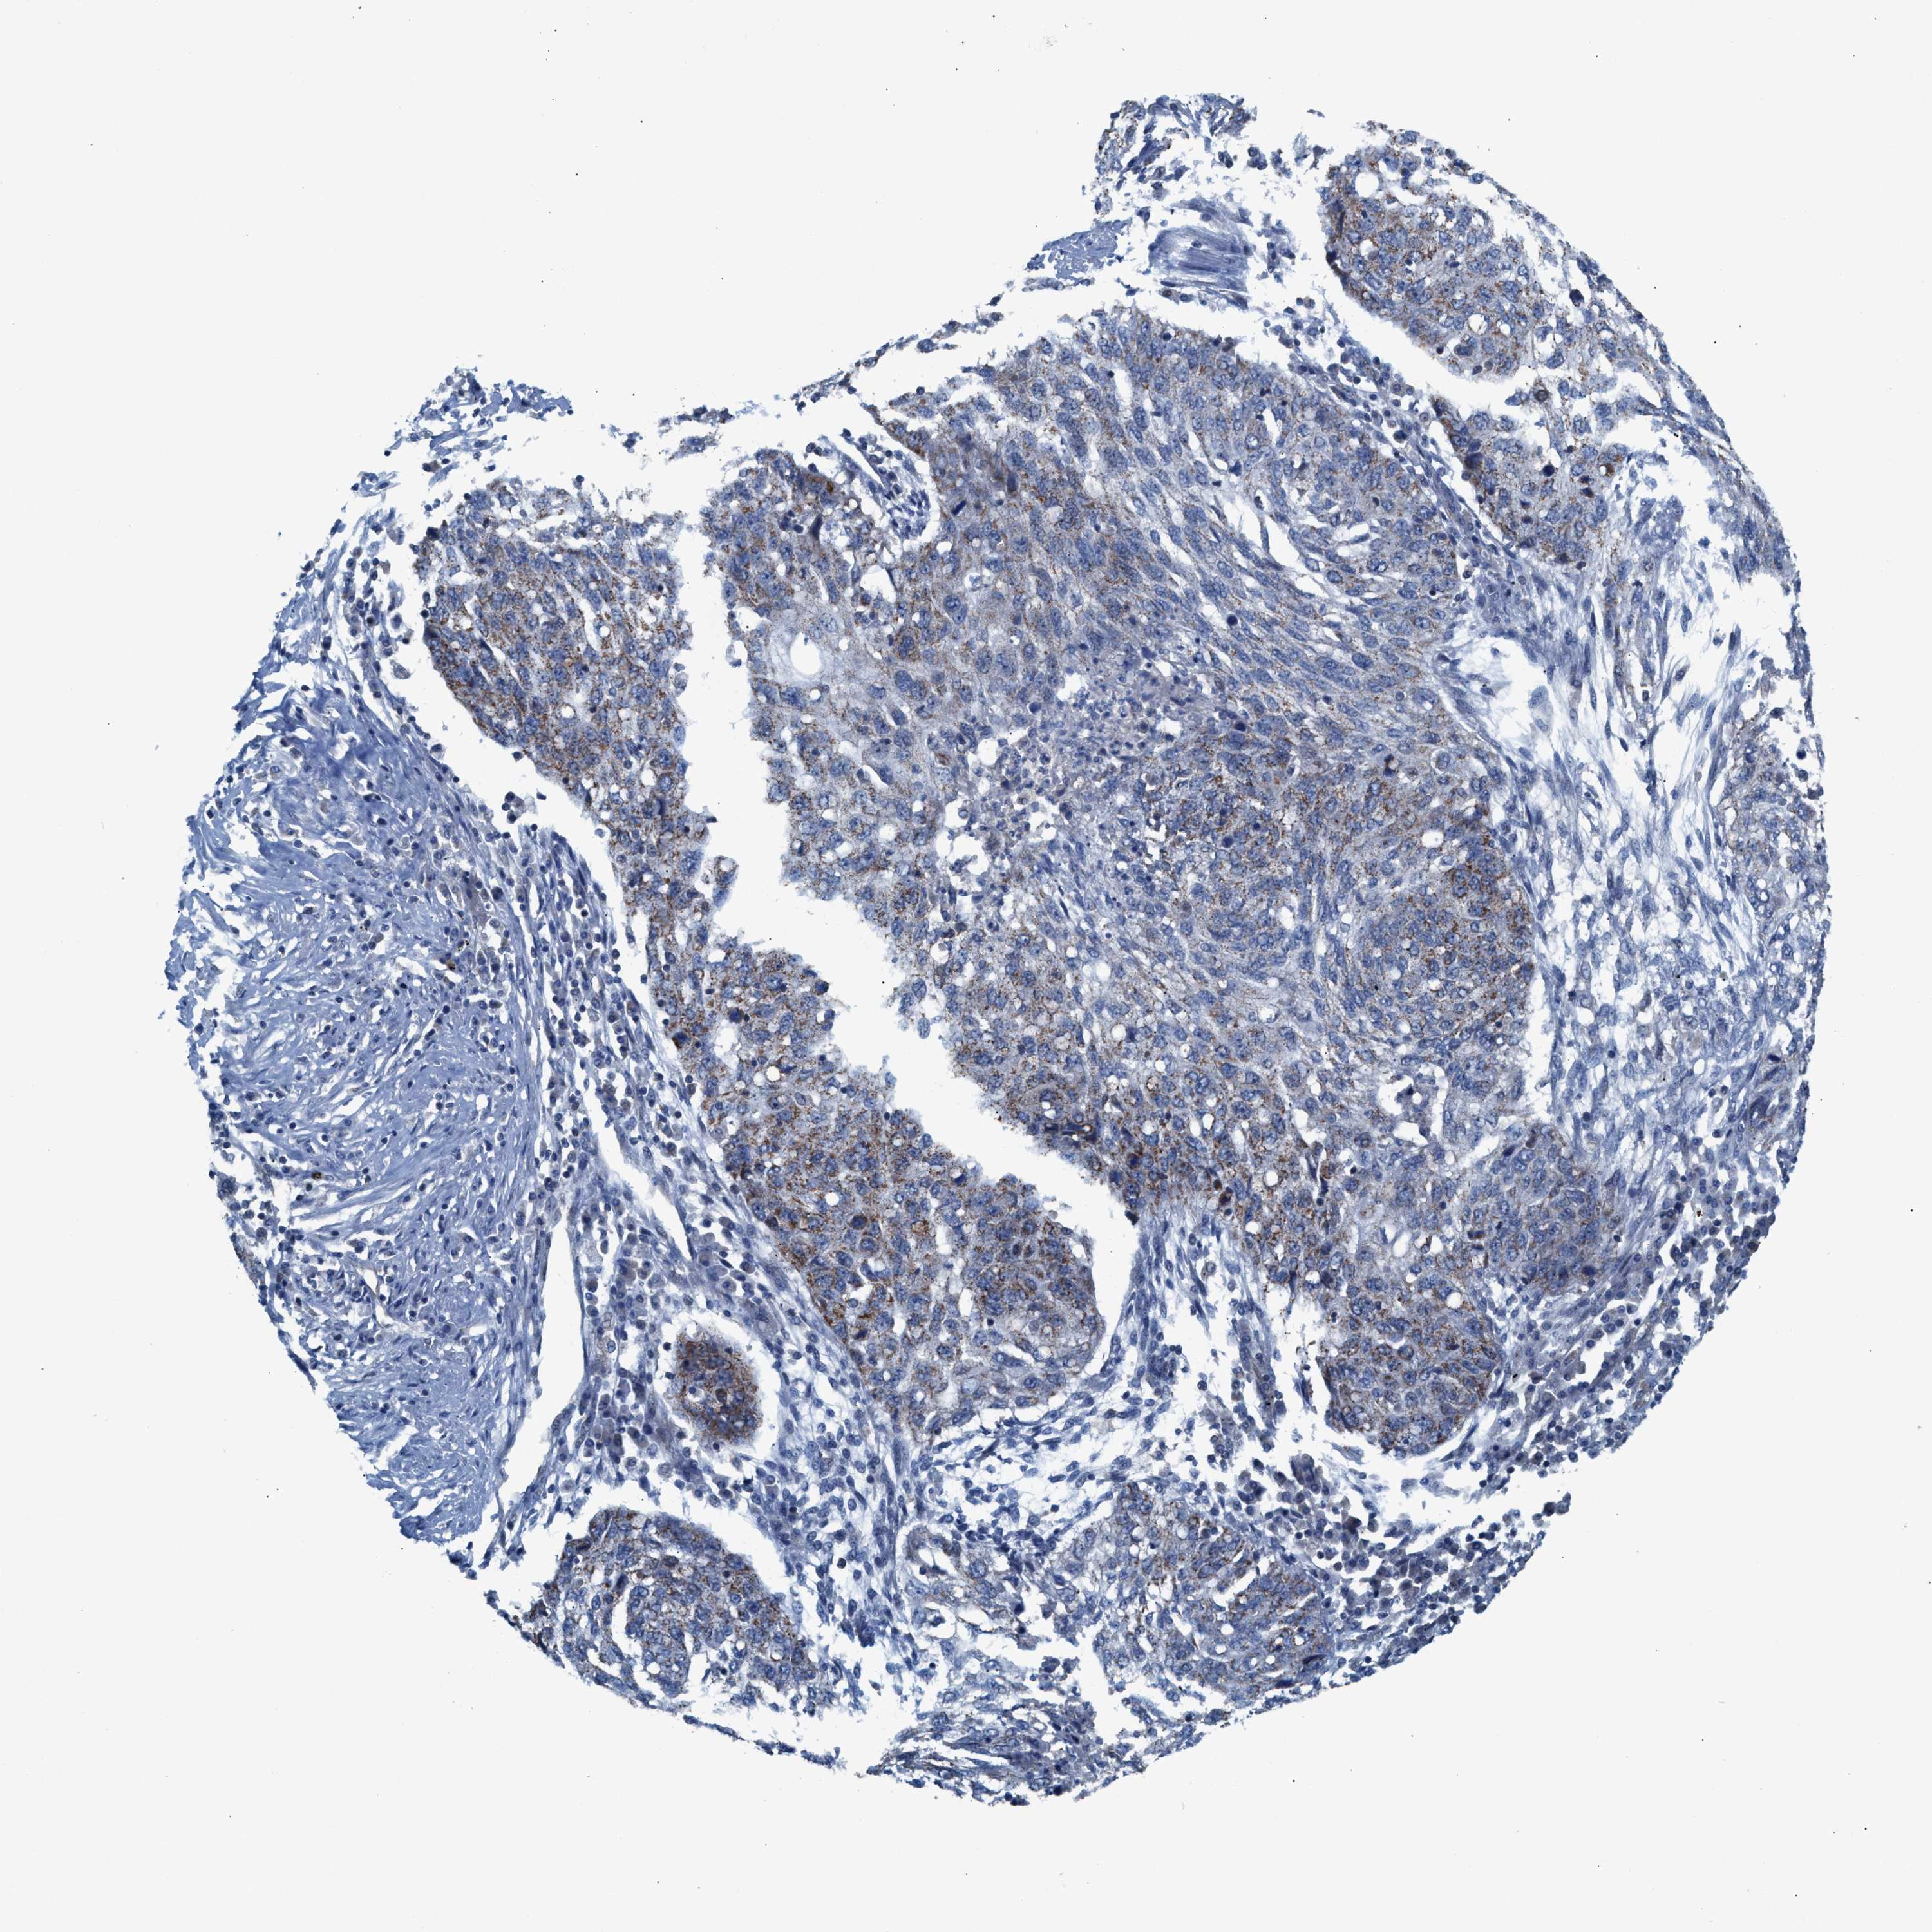

CANCER LUNG CANCER Show tissue menu

LUAD TCGA LUAD VALIDATION LUSC TCGA LUSC VALIDATION PROTEIN LUAD CPTAC PROTEIN LUSC CPTAC PROTEIN EXPRESSION